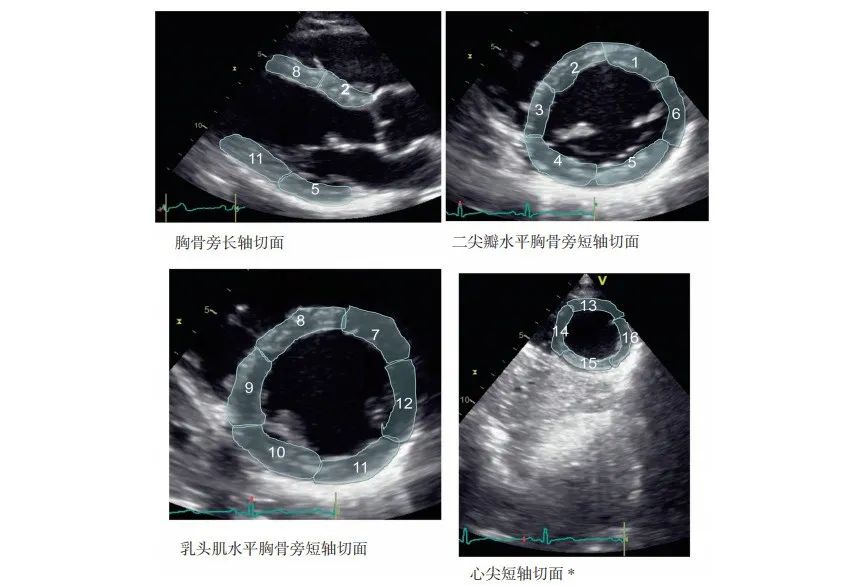

在短轴切面上,将基底环和中间环分为六个区域(每个区域占左心室周长的60°),将心尖环水平分为四个区域(每个区域占该水平的左心室周长的90°),区域的分割开始于室间隔和右心室游离壁的前交界处并逆时针旋转,这样就形成了16个节段,分别为:

基底环:前壁基底段(1)、前间隔基底段(2)、下间隔基底段(3)、下壁基底段(4)、下侧壁基底段(5)、前侧壁基底段(6)

中间环:前壁中间段(7)、前间隔中间段(8)、下间隔中间段(6)、下壁中间段(10)、下侧壁中间段(11)、前侧壁中间段(12)

心尖环:前壁心尖段(13)、间隔心尖段(14)、下壁心尖段(15)、侧壁心尖段(16)

标准二维超声心动图观察左心室各心肌节段的定位,各个节段的数字对应前面的文字,心尖短轴切面通常从心尖处获得,移动探头让其高于传统四腔心切面一个肋间,并将探头向右肩倾斜,以获得右心室尖端消失处的环形切面